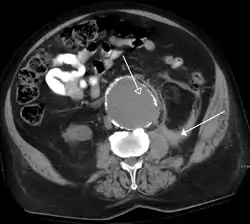

O scanare CT care prezintă anevrism de aortă abdominală ruptă | |